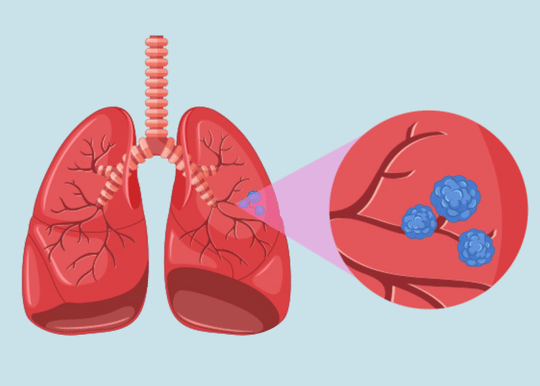

representa un avance revolucionario en el campo de la medicina, ofreciendo nuevas esperanzas para pacientes con insuficiencias...